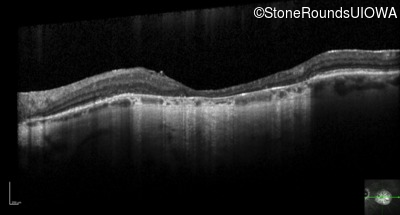

Optical Coherence Tomography - Right - 20/50 -1

Exemplar / OCT Stack

Optical Coherence Tomography - Left - 20/80 +1